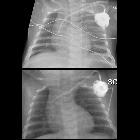

Fehllage Portkatheter

Bisweilen sieht man auch primäre Fehllagen eines frisch gelegten Portkatheters.

Nicht alle Portkatheter sind in der primär operativ erreichten Position stabil. Eine Dislokation des Portkatheters kann bei kurz angelegtem Katheter, der nur wenig nach kaudal in die V. cava superior zeigt, nach kranial in die V. jugularis vorkommen. Auch in andere Richtungen bzw. Venen (z. B. V. brachiocephalica sinistra) kann ein Katheter umschlagen. Solche Fehllagen können ggf. perkutan korrigiert werden. Wenn jedoch ein Katheter primär in der V. cava superior zu kurz ist, kann es (z. B. beim Husten) häufig zu Rezidiv-Fehllagen kommen.